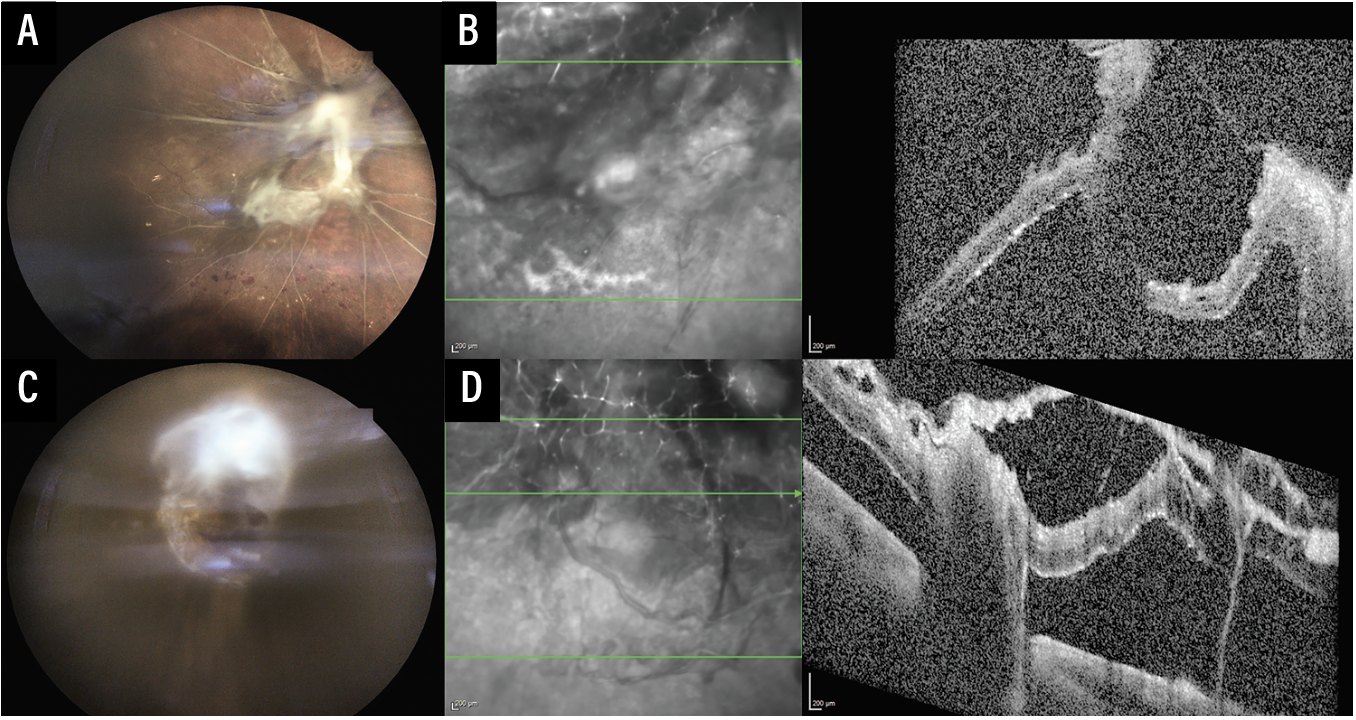

Two years later, the patient presented to our clinic with worsening vision, now reduced to hand motions in both eyes. Examination showed bilateral fovea-involving tractional retinal detachments (Figure 2). Further questioning revealed that the patient was unemployed, faced housing and food instability, and depended on public and Medicaid transportation to get to medical appointments. Surgical intervention was recommended; however, the patient’s prognosis for visual recovery was dismal, and his case illustrates how much worse outcomes can be when patients are lost to follow-up, often due to challenges related to social determinants of health.

| Figure 2. The patient was lost to follow-up and returned two years later with worsening vision in both eyes to hand motions. Fundus photos of the right (A) and left (C) eyes show progressive proliferative diabetic retinopathy with bilateral fovea-involving tractional retinal detachments with thick fibrovascular membranes extending from the optic nerve head to both the superotemporal and inferotemporal arcades. Optical coherence tomography of the right (B) and left (D) eyes through the macula confirm tractional retinal detachments, showing the retinal layers pulled anteriorly in a tent-like configuration with complete loss of the normal foveal contour. |